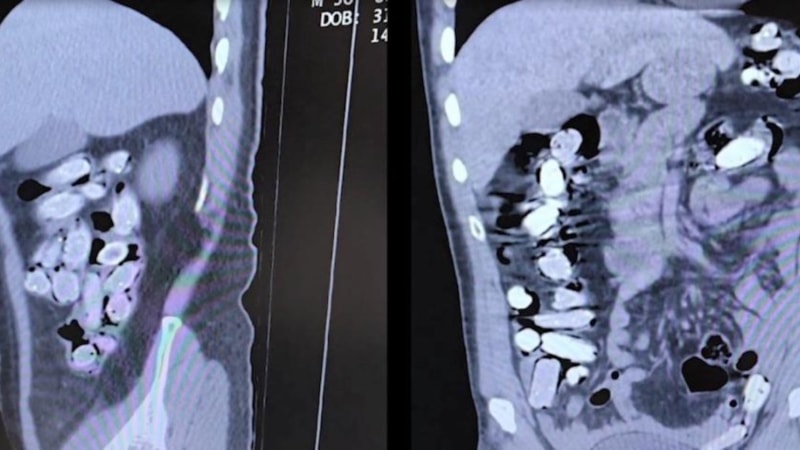

Tatvan Devlet Hastanesine sevk edilen şüphelilerin röntgen ve tomografi görüntülerinde mide ile bağırsaklarında çok sayıda yabancı cisim bulunduğu tespit edildi.

Yapılan tıbbi müdahale ile şüphelilerin paketleyerek yuttuğu toplam 96 adet daralı ağırlığı 1 kilogram 340 gram Afyon sakızına el konuldu.